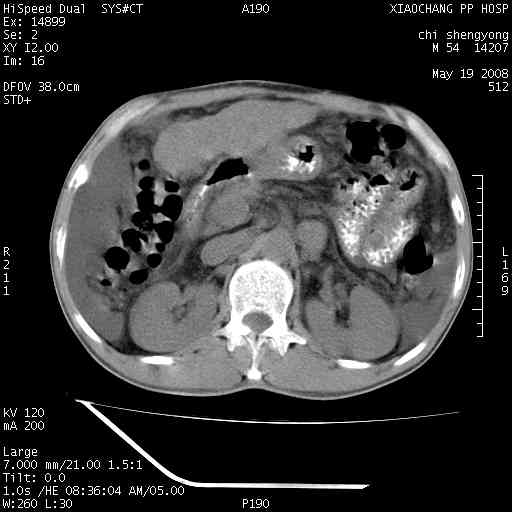

以下是引用zjzjr在2008-5-21 10:52:00的发言:[br]肝左叶巨块型肝癌伴门静脉左支瘤栓形成.肝硬化、腹水,胃底静脉曲张,脾术后改变。

以下是引用随光逐影在2008-5-21 16:20:00的发言:[br]1)肝左叶肝癌伴门静脉左支瘤栓形成,腹膜后淋巴结转移。2)肝硬化、腹水、胃底静脉曲张。3)胆囊炎。4)脾脏缺如,为切除术后所致。